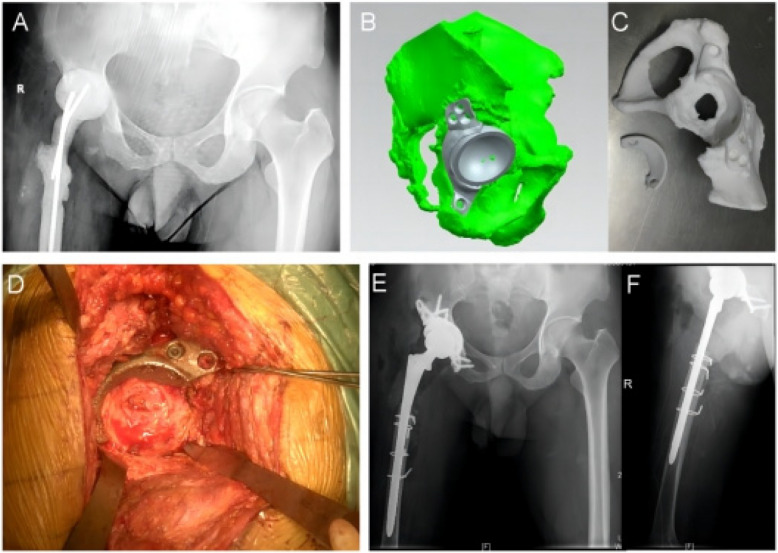

Methods: We reviewed three cases of Paprosky type III acetabular defects reconstructed using personalized 3D-printed porous titanium alloy augments. Finite element analysis (FEA) simulated the defects, utilizing a commercial augment as a control. Stress distribution within the augments, fixation screws, acetabular cups, and surrounding bone was analyzed under simulated single-leg standing (1 × body weight), walking (4 × BW), and jogging (6 × BW) loading conditions, with comparisons made to the control.

Results: Under all loading conditions, the peak stresses observed on the augment screws and acetabular cups in all three cases were lower than the buckling strength of titanium alloy and were consistently lower than those recorded in the control group. This indicates that the personalized augments provided stable support for acetabular cup fixation, aiding in the restoration of the hip rotation center and lower limb length.